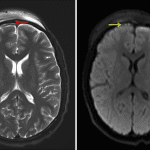

- Thin, mildly T2 hyperintense subdural collection overlying the anterior right frontal lobe with associated restricted diffusion, measuring 2 mm in thickness

- Thin, peripherally enhancing subperiosteal collection with associated restricted diffusion along the outer table of the frontal bone on the right just superior to the right frontal sinus with extensive surrounding edema and soft tissue enhancement extending inferiorly into the right greater than left periorbital soft tissues

- Extensive mucosal thickening and opacification of the right frontal, right ethmoid, and right maxillary sinuses with associated internal restricted diffusion

- Complicated frontal sinusitis with subdural empyema

Acute right anterior drainage pathway sinusitis complicated by a thin right frontal convexity subdural empyema with surrounding pachymeningitis, a thin right frontal subperiosteal abscess, and right greater than left frontal scalp and periorbital cellulitis. No evidence of cerebritis or brain abscess.